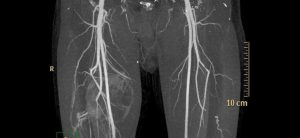

КТ-ангиография брюшной полости, нижних конечностей

Компьютерная томографическая ангиография (КТА) используется для изучения кровотока практически во всех областях тела. Вы можете исследовать кровеносные сосуды головного мозга, шеи, груди, живота, таза и конечностей. Этот метод требует использования контрастного вещества, вводимого под давлением с высокой скоростью. Доступны различные методы контрастирования. Контраст можно вводить в периферическую вену, а сосудистое русло можно исследовать после того, …